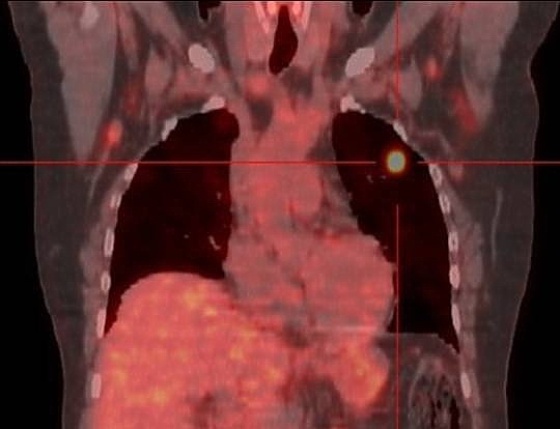

PET-bilde av en person med mulig lungekreft. |

Ved kreftdiagnostikk brukes stoff som lettere samler seg ved kreftsvulster enn i normalt vev. Når pasienten så blir avfotografert vil man kunne se hvor kreftcellene befinner seg. I dag brukes følsomme dataplater i stedet for film, fordi avansert billedbehandling i datamaskin gir bedre bilder.

PET-skanneren er en videreutvikling av gammakameraet. Den har en roterende enhet som gir bilder fra alle vinkler rundt en person, men til forskjell fra CT-skanneren kommer strålingen fra innsiden av personen som undersøkes. Det brukes normalt radioaktive isotoper som er knyttet sammen med druesukker. Det gjør at radioaktiviteten vil samle seg der aktiviteten i cellene er størst, nemlig de områdene som trenger energi i form av sukker.

- Med PET-skanning vil man kunne se hvor kreftcellene befinner seg i kroppen, forteller overlege Erik Traasdahl. Han er leder av nukleærmedisinsk seksjon ved Radiologisk avdeling på UNN.